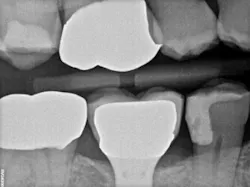

When decay arises on adjacent teeth, dentists must evaluate their treatment options. I have found there is a high degree of difficulty restoring large Class II or interproximal lesions with direct composites, especially when the decay is on premolars. It is much more predictable to restore Class IIs on molars with tight contacts, but it can still be difficult. I have tried full matrix bands and multiple sectional matrix bands, but I can’t create a nice contour with a tight contact. I have even tried traditional composites and bulk fill without great success. See Figures 1 and 2 showing my open contacts with direct composite.